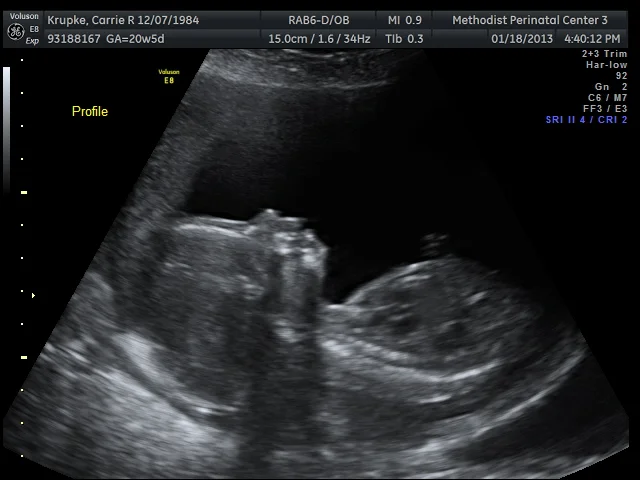

Greg + Cindy :: Abigail